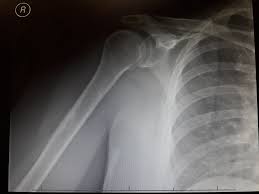

omuz yirtigi tipleri omuzda lif yirtilmasi doktor fizik